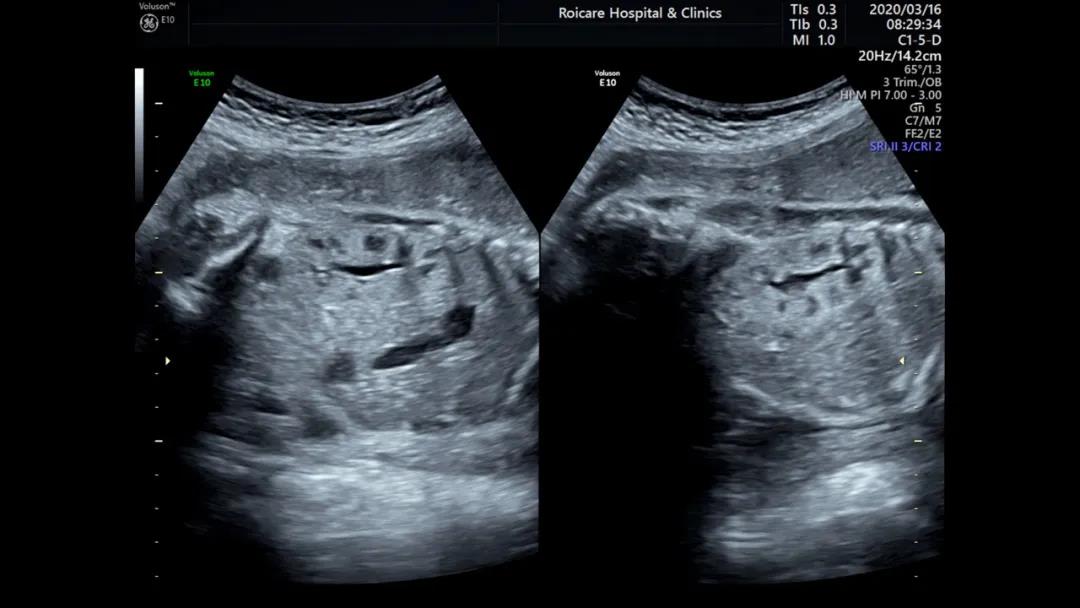

4.肾脏皮质回声增强

肾脏皮质回声增强往往是多囊肾、肾发育不良、一些综合征的表现(Meckel-Gruber综合征)、染色体异常等疾病的一种表现。当看到肾皮质强回声时,需要专业的产前诊断医生给您进一步建议,包括我们产前诊断羊水穿刺,甚至需要家族做泌尿系超声检查,协助一些遗传性疾病的诊断。

那是不是肾皮质强回声的胎儿都不能要了?当然不是,有一些正常肾脏发育中也存在这样变异,同时某些肾脏的问题预后也是比较好的,所以宝妈们不要轻易地放弃,也不要盲目的赌博。来产前诊断门诊,让专业的产前诊断医生给您专业的解释和评估。